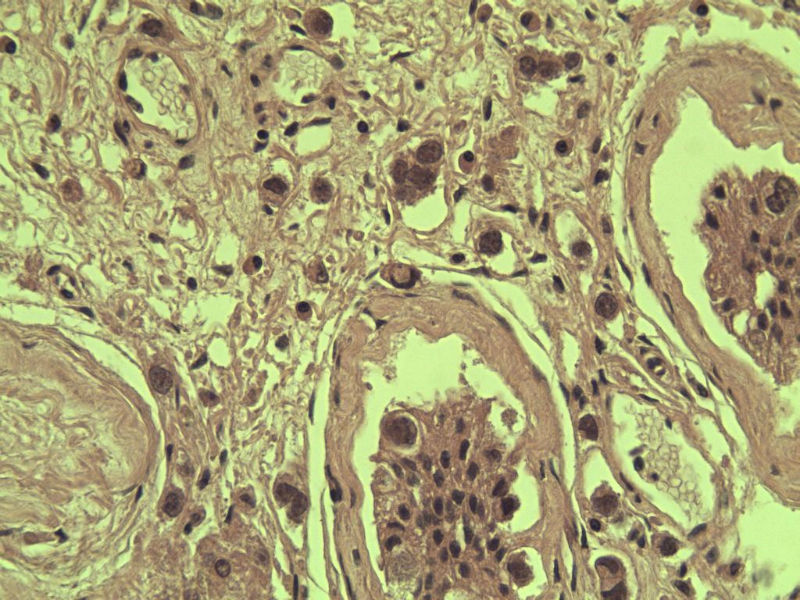

男 27岁 腹腔隐睾 5*3*2 cm, 切面灰红灰黄、实性、质中,请各位老师看看,是精原细胞瘤吗?感觉不像.